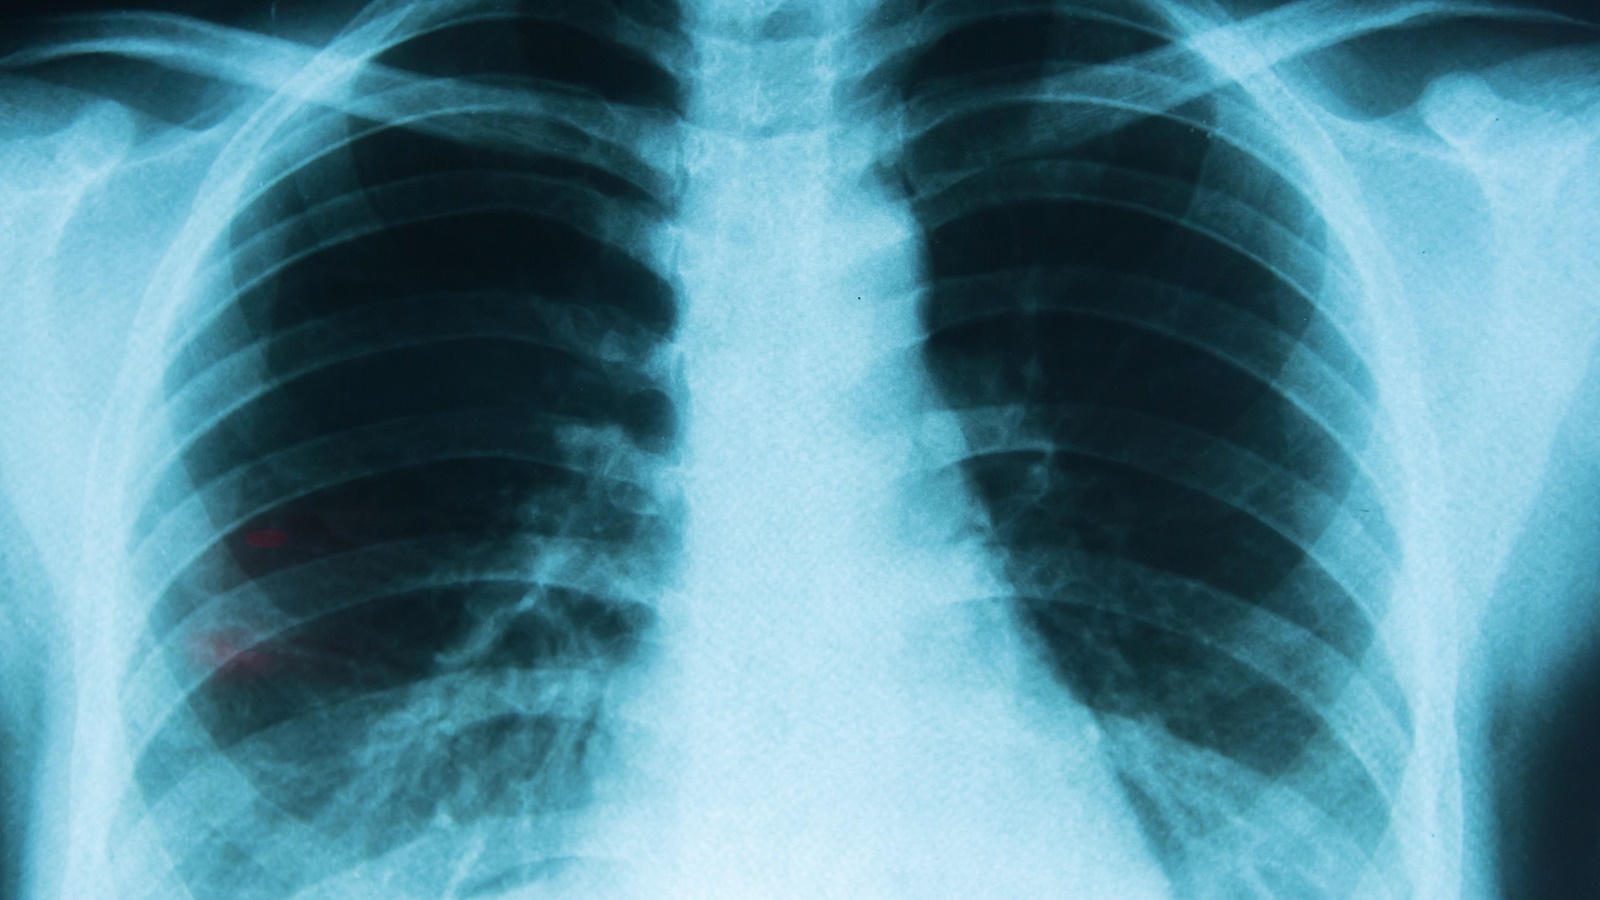

La Administración Nacional de Medicamentos, Alimentos y Tecnología Médica (ANMAT) anunció la aprobación del fármaco Amivantamab para el tratamiento del cáncer de pulmón de células no pequeñas (CPCNP), un avance significativo en la lucha contra una de las formas más mortales de cáncer.

El cáncer de pulmón es la forma más prevalente de cáncer en Argentina y una de las más mortales. Según el Ministerio de Salud de la Nación, se proyecta un aumento del 20% en los casos para el año 2030, lo que destaca la importancia de innovaciones terapéuticas como el Amivantamab en la mejora de las tasas de supervivencia y la calidad de vida de los pacientes.